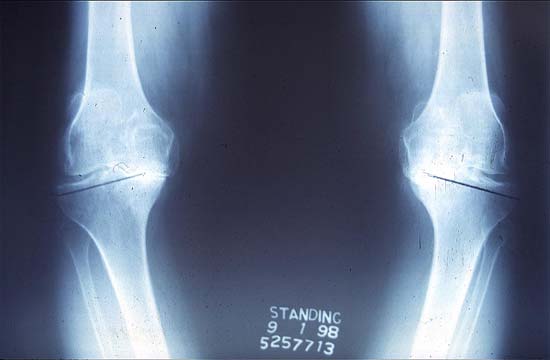

70岁,软骨破坏,严重双膝内翻畸形

双膝关节X线片显示关节软骨破坏,间隙消失,膝内翻

术后X线片,假体用骨水泥固定显示膝内翻被纠正